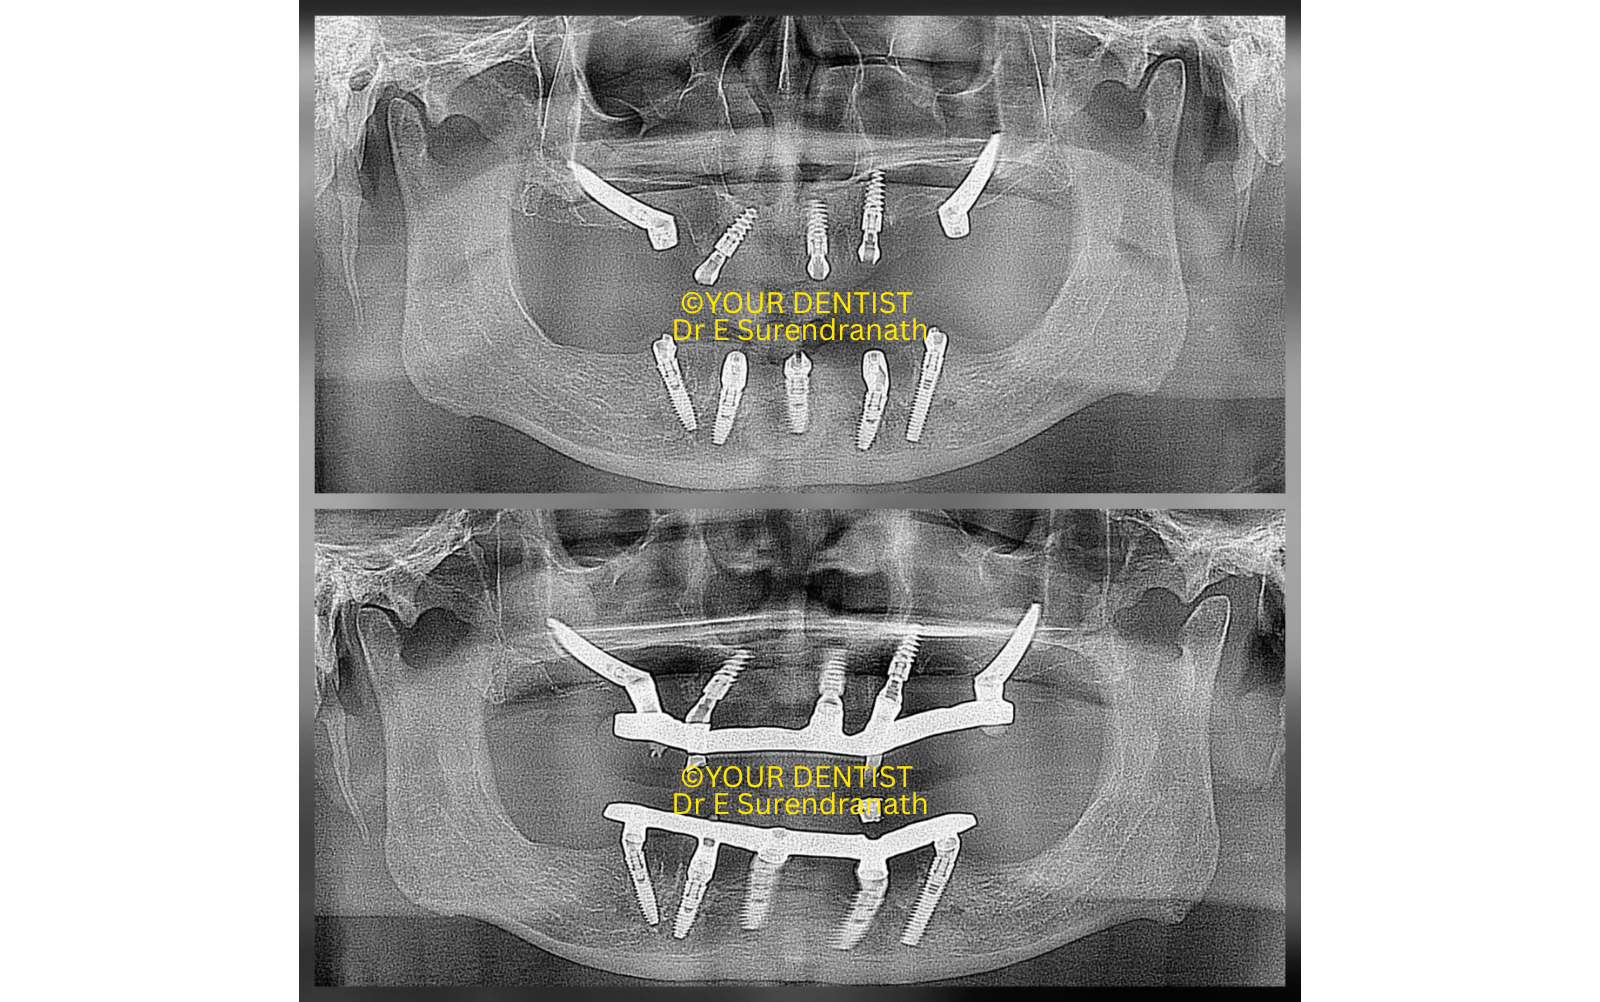

One of the important features of this case was the posterior positioning of the zygomatic implants in the molar region, following the distal or molar positioning philosophy often associated with Dr Petrungaro. This kind of posterior implant emergence can significantly improve antero-posterior spread and reduce the need for long distal cantilevers in the prosthesis. Here, in this case, you can see it for yourself that we completely avoided the cantilever effect by placing the zygomatic implants at the molar region, as seen in fig 2.

Fig 2

Immediate loading full arch dental implant prosthesis

After careful planning, the upper arch was rehabilitated using bilateral zygomatic implants along with anterior conventional implants in the residual maxillary bone. The zygomatic implants were placed to engage the zygomatic bone and provide strong remote anchorage, while the anterior implants helped create a well-distributed full-arch support system.

The post-operative radiographs demonstrate stable implant placement in both arches, including bilateral zygomatic anchorage in the maxilla and a full-arch framework-supported prosthetic plan. The prosthetic images also show a clean and functional fixed restoration with screw-access openings positioned for full-arch loading.